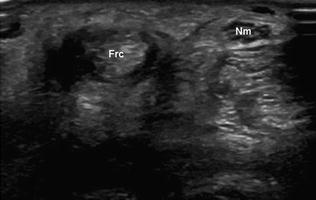

На внутренней стороне запястья расположены три сухожилия, находящиеся близко к запястному каналу: лучевой сгибатель запястья (Frc), длинная ладонная мышца (Pl) и локтевой сгибатель запястья (Fuc). Внизу представлены схемы: а — диаграмма, б — сонограмма.

Лучевой сгибатель запястья — это длинное цилиндрическое сухожилие, которое начинается на медиальном надмыщелке плечевой кости через сухожилие общего сгибателя и прикрепляется к основаниям второй и третьей пястных костей [1]. Оно окружено синовиальной оболочкой, которая начинается приблизительно на 3 см выше запястья и заканчивается на месте крепления. Наиболее распространённое заболевание, которое затрагивает лучевой сгибатель запястья, — это теносиновит, возникающий из-за чрезмерной нагрузки, травм или воспалительных процессов, а также запястно-пястной артропатии. Клинически это проявляется болью в ладонной области запястья у лучевой кости, часто с местным отеком. На основе лишь физикального осмотра синовит лучевого сгибателя запястья может быть ошибочно принят за ганглий. Эта ошибка может быть исправлена с помощью сонографического исследования, демонстрирующего характерные признаки синовита.

При тендосиновите лучевого сгибателя запястья ультразвуковое исследование показывает анэхогенную область вокруг сухожилия (Frc).